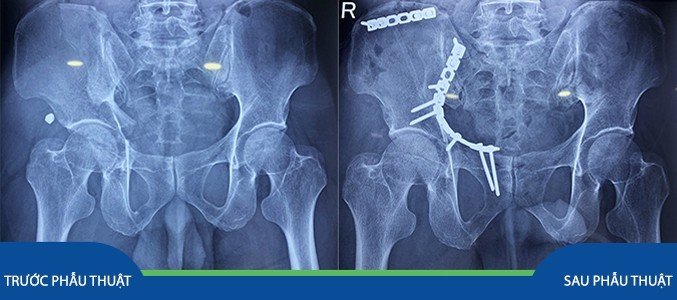

Bệnh nhân H.V.H. (67 tuổi) nhập viện trong tình trạng sốc đa chấn thương sau tai nạn giao thông. Bệnh nhân được người nhà đưa vào cấp cứu tại Bệnh viện Chấn thương Chỉnh hình Nghệ An. Sau khi được sơ cứu và hồi sức chống sốc và thực hiện cận lâm sàng, bệnh nhân được chẩn đoán: Đa chấn thương: Chấn thương ngực kín: Gãy xương sườn II, III bên trái, gãy xương sườn IX, X, XI bên phải/ Gãy xương đòn trái/ Chấn thương khung chậu: Gãy ngành chậu mu, ngồi mu, xương cánh chậu phải, vỡ ổ cối phải, gãy hở 2 mắt cá chân phải. Bệnh nhân được các bác sỹ thực hiện phẫu thuật cắt lọc xử lý gãy hở thì đầu, sau đó được điều trị tích cực chống phù nề, giảm đau và lên kế hoạch phẫu thuật kết hợp xương gãy ổ cối.

Sau thời gian hội chẩn và lên kế hoạch phẫu thuật tỉ mỉ, Ekip phẫu thuật bao gồm: BS. Nguyễn Mạnh Linh – Phó trưởng khoa Chi dưới, BSCKI. Nguyễn Hữu Đức, cùng các bác sỹ và kỹ thuật viên khác đã phẫu thuật kết hợp xương ổ cối và cánh chậu cho bệnh nhân. Ca phẫu thuật thành công mỹ mãn. Một tuần sau phẫu thuật, bệnh nhân có thể tự ngồi được, chức năng thụ động khớp háng bên phẫu thuật đạt được tối đa, bệnh nhân có thể tự ngồi và vận động nhẹ tại giường.